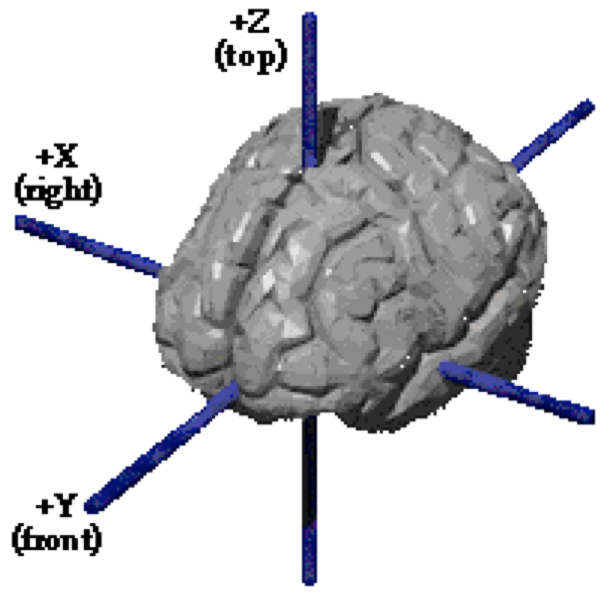

| X | Y | Z |

|---|---|---|

| 12 | 57 | -6 |

| 33 | 21 | 15 |

| 24 | -6 | 51 |

| 28 | 10 | 18 |

Yarkoni et al, 2011, Nature Methods

Gorgolewski et al., 2015, Frontiers in Neuroinformatics